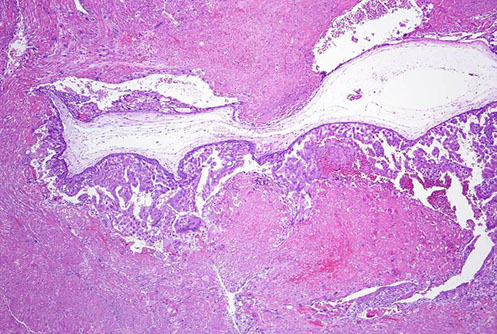

Choriocarcinoma can arise from within a placenta kind of as an in-situ lesion that looks like a white nodule; this is an example of an intraplacental choriocarcinoma in term non-molar placenta

Intraplacental choriocarcinoma in term non-molar placenta. See here how it is associated with the normal placenta